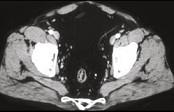

问题 男,41岁,腹痛、腹泻、腹胀、脓血便、里急后重、疲乏无力,结合图像,选择最可诊断 ( )

选项 A、假膜性肠炎 B、结肠淋巴瘤 C、结肠克罗恩病 D、结肠结核 E、溃疡性结肠炎

答案 E